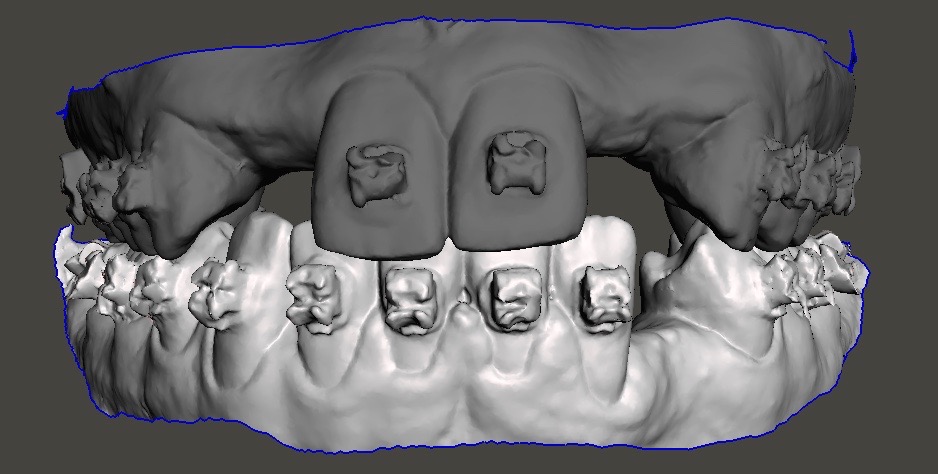

Fig 18. Scans of patient while still in orthodontic brackets.

Figure 18

Digital impressioning and digitally driven treatment planning and execution are quickly becoming the norm in orthodontic treatment. This allows for interdisciplinary treatment to be performed digitally, even in the presence of brackets and wires. As an example, a 13-year-old patient presented with congenitally missing maxillary lateral incisors, as well as tooth No. 22. After discussing various treatment options, the patient and her parents decided to maintain the edentulous spaces with resin-bonded fixed partial dentures (RBFPDs) until the patient was old enough for dental implants. At completion of orthodontic treatment but before removal of brackets and wires, the patient was digitally scanned (Figure 18). Her models were manipulated in orthodontic software to remove the brackets, and the case was imported into restorative CAD software for design and fabrication of the RBFPDs (Figure 19). The e.max RBFPDs were milled and subsequently delivered immediately after bracket removal (Figure 20).